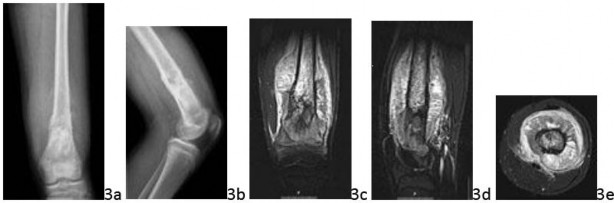

Question 4 A 12-year-old girl has a 6-month history of a painful expanding mass in the right lateral ankle. A clinical photograph, radiograph, MRI scans, and histology specimens are seen in Figures 4a through 4f. What is the most appropriate management?

Question 4 A 12-year-old girl has a 6-month history of a painful expanding mass in the right lateral ankle. A clinical photograph, radiograph, MRI scans, and histology specimens are seen in Figures 4a through 4f. What is the most appropriate management?

DISCUSSION: The radiograph shows an expansile radiolucent lesion without matrix production or a periosteal reaction. On close inspection, there are subtle internal septations on the mortise view. The MRI scans show heterogeneous septated areas with prominent fluid-fluid levels. The histopathology on low power shows villous projections and prominent clefts, whereas the high power view reveals prominent spindled stromal cells and interspersed multinucleated giant cells. This is an

aneurysmal bone cyst

. The treatment of aneurysmal bone cyst is generally intralesional surgery (eg, curettage). However, for patients with large destructive lesions in expendable bones such as the fibula, excision is preferred. The main differential diagnosis in this patient is

telangiectatic osteosarcoma

. Radiographs of telangiectatic osteosarcoma show geographic bone lysis, a wide zone of transition, and matrix mineralization. Under the microscope, telangiectatic osteosarcoma exhibits pleomorphic cells with at least focal malignant osteoid production.

Telangiectatic osteosarcoma is treated with chemotherapy and wide excision. The Preferred Response to Question # 4 is 1.